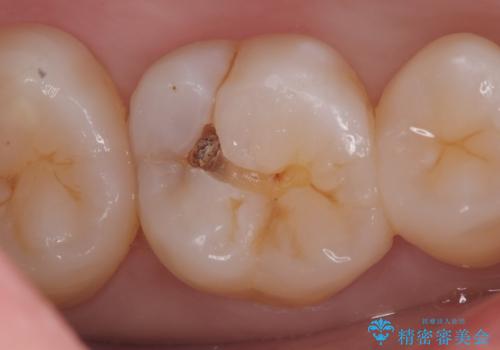

- 主訴:奥歯の噛む面が虫歯になっている。プラスチックの材料で治療可能と言われたが、劣化してまた虫歯になるのが怖いのでセラミックの詰め物にしたい。

咬合面にう蝕があり、CR修復・各種インレーの特徴を説明し、審美性・適合性の良いセラミックインレーでのやり替えとなりました。

咬合面のみのう蝕の場合CR(コンポジットレジン)修復を行うことが多いですが、CRは経年劣化しやすく二次う蝕の可能性を帯びています。それに比べセラミックは着色や収縮が少なく、経年劣化しにくい材料のため、今回はセラミックインレーでの治療となりました。